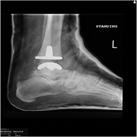

When conservative (non-operative) measures such as activity modification, painkillers and orthotic supports are no longer adequate, surgery may become necessary. Ankle or other hind foot joint stiffening operation (fusion or arthrodesis, Fig 2) has been the surgery of choice and can be performed both as an open and as a keyhole procedure. The trade-off is pain reduction for increased stiffness but other than in the knee or hip joint fusion is relatively well tolerated and the functional results are surprisingly good. More recently results from modern ankle replacing prostheses (Fig 3) have been improving, offering this as a suitable alternative for selected patients.